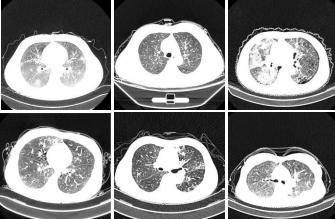

CC-19 COVID-19 Dataset

CC-19 is a small dataset related to COVID-19. The dataset contains 34,006 CT scans (images) involving 98 individuals, of which 28,395 CT scans belong to COVID-positive patients.